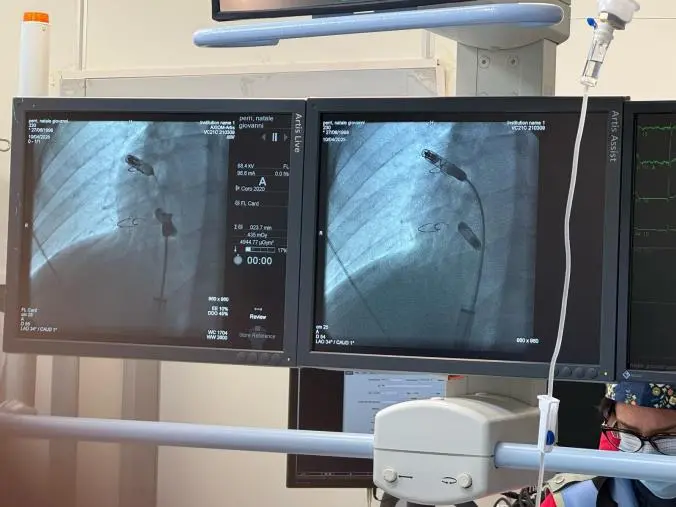

Storie di buona sanità alla Dulbecco. Buona sanità all’avanguardia e a servizio dei pazienti . E’ stata eseguita presso l’Unità Operativa di Cardiologia UTIC del P.O. Pugliese-Ciaccio innovativo impianto di pacemaker senza cateteri (PM leadless).

La Direzione Generale coinvolta dal Direttore della Cardiologia del nosocomio cittadino, dott. Vincenzo Ciconte, ha consentito l’applicazione di un innovativo pacemaker bicamerale leadless in un giovane paziente, già operato in età pediatrica al cuore, le cui concomitanti patologie non consentivano l’utilizzo della tecnologia transvenosa routinariamente utilizzata.

La singolarità dell’impianto, tra i primi in Italia, risiede nell’utilizzo di un dispositivo che non necessità di collegamenti tra l’apparecchio e il cuore, avvalendosi di due device (in atrio e ventricolo destro) che si avvitano direttamente all’interno del cuore e si avvicinano il più possibile alla stimolazione fisiologica cardiaca. Il brillante risultato della procedura è stato condiviso con la famiglia dell’assistito, appena dimesso.